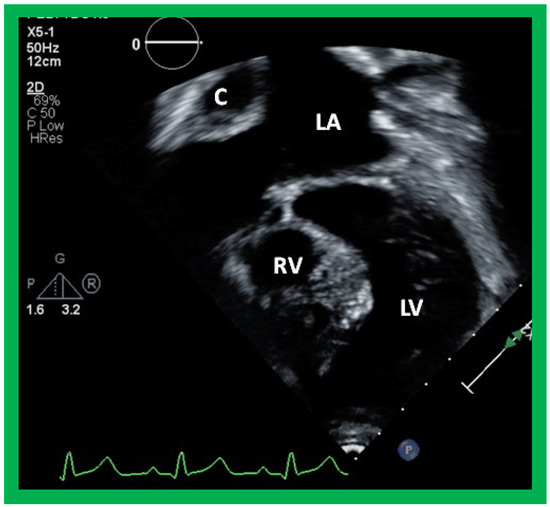

5.3. Echocardiographic Evaluation Following Bidirectional Glenn

Following bidirectional Glenn, the LV size is likely to decrease (normalize) and LV should maintain normal systolic function. This is because of decreased LV volume overload following bidirectional Glenn and the removal of aorto–pulmonary shunt. The 2D imaging of the bidirectional Glenn is difficult to accomplish, but color flow imaging (Figure 25A, Figure 26B, and Figure 27B) from a suprasternal notch or high parasternal views will help image the bidirectional Glenn. Low pulsed Doppler velocity across the superior vena cava (SVC)–PA junction (Figure 25B and Figure 26C) would indicate no obstruction. Turbulent and high velocity Doppler flow suggests the obstruction of the bidirectional Glenn shunt. The size of the branch PAs may be assessed with a combination of 2D and color flow imaging (Figure 26, Figure 27 and Figure 28).

Angiographic counter parts of the bidirectional Glenn are shown, in Figure 29, to have better comprehension of the anatomy of the bidirectional Glenn.